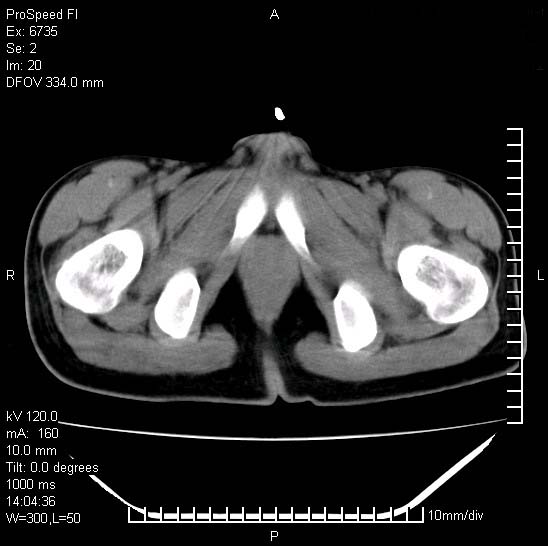

患者自诉胯部疼痛两年余,在当地服用中药,半月前至本院考虑骶髂关节结核,给予抗痨治疗。现发展至右下肢疼痛明显,活动受限,以膝关节处明显,拍膝关节平片无明显异常。

两侧骶骼关节改变,考虑强直性脊炎

左侧骶髂关节面限局性骨破坏,边缘硬化关节腔见钙化物;不出外tb

右侧骶髂关节也有类似改变,只是较左侧轻,首先考虑强直性脊柱炎,不除外结核,建议作hla-b27检查。

典型强脊炎改变,髋关节亦有累及

符合强直性脊柱炎表现。